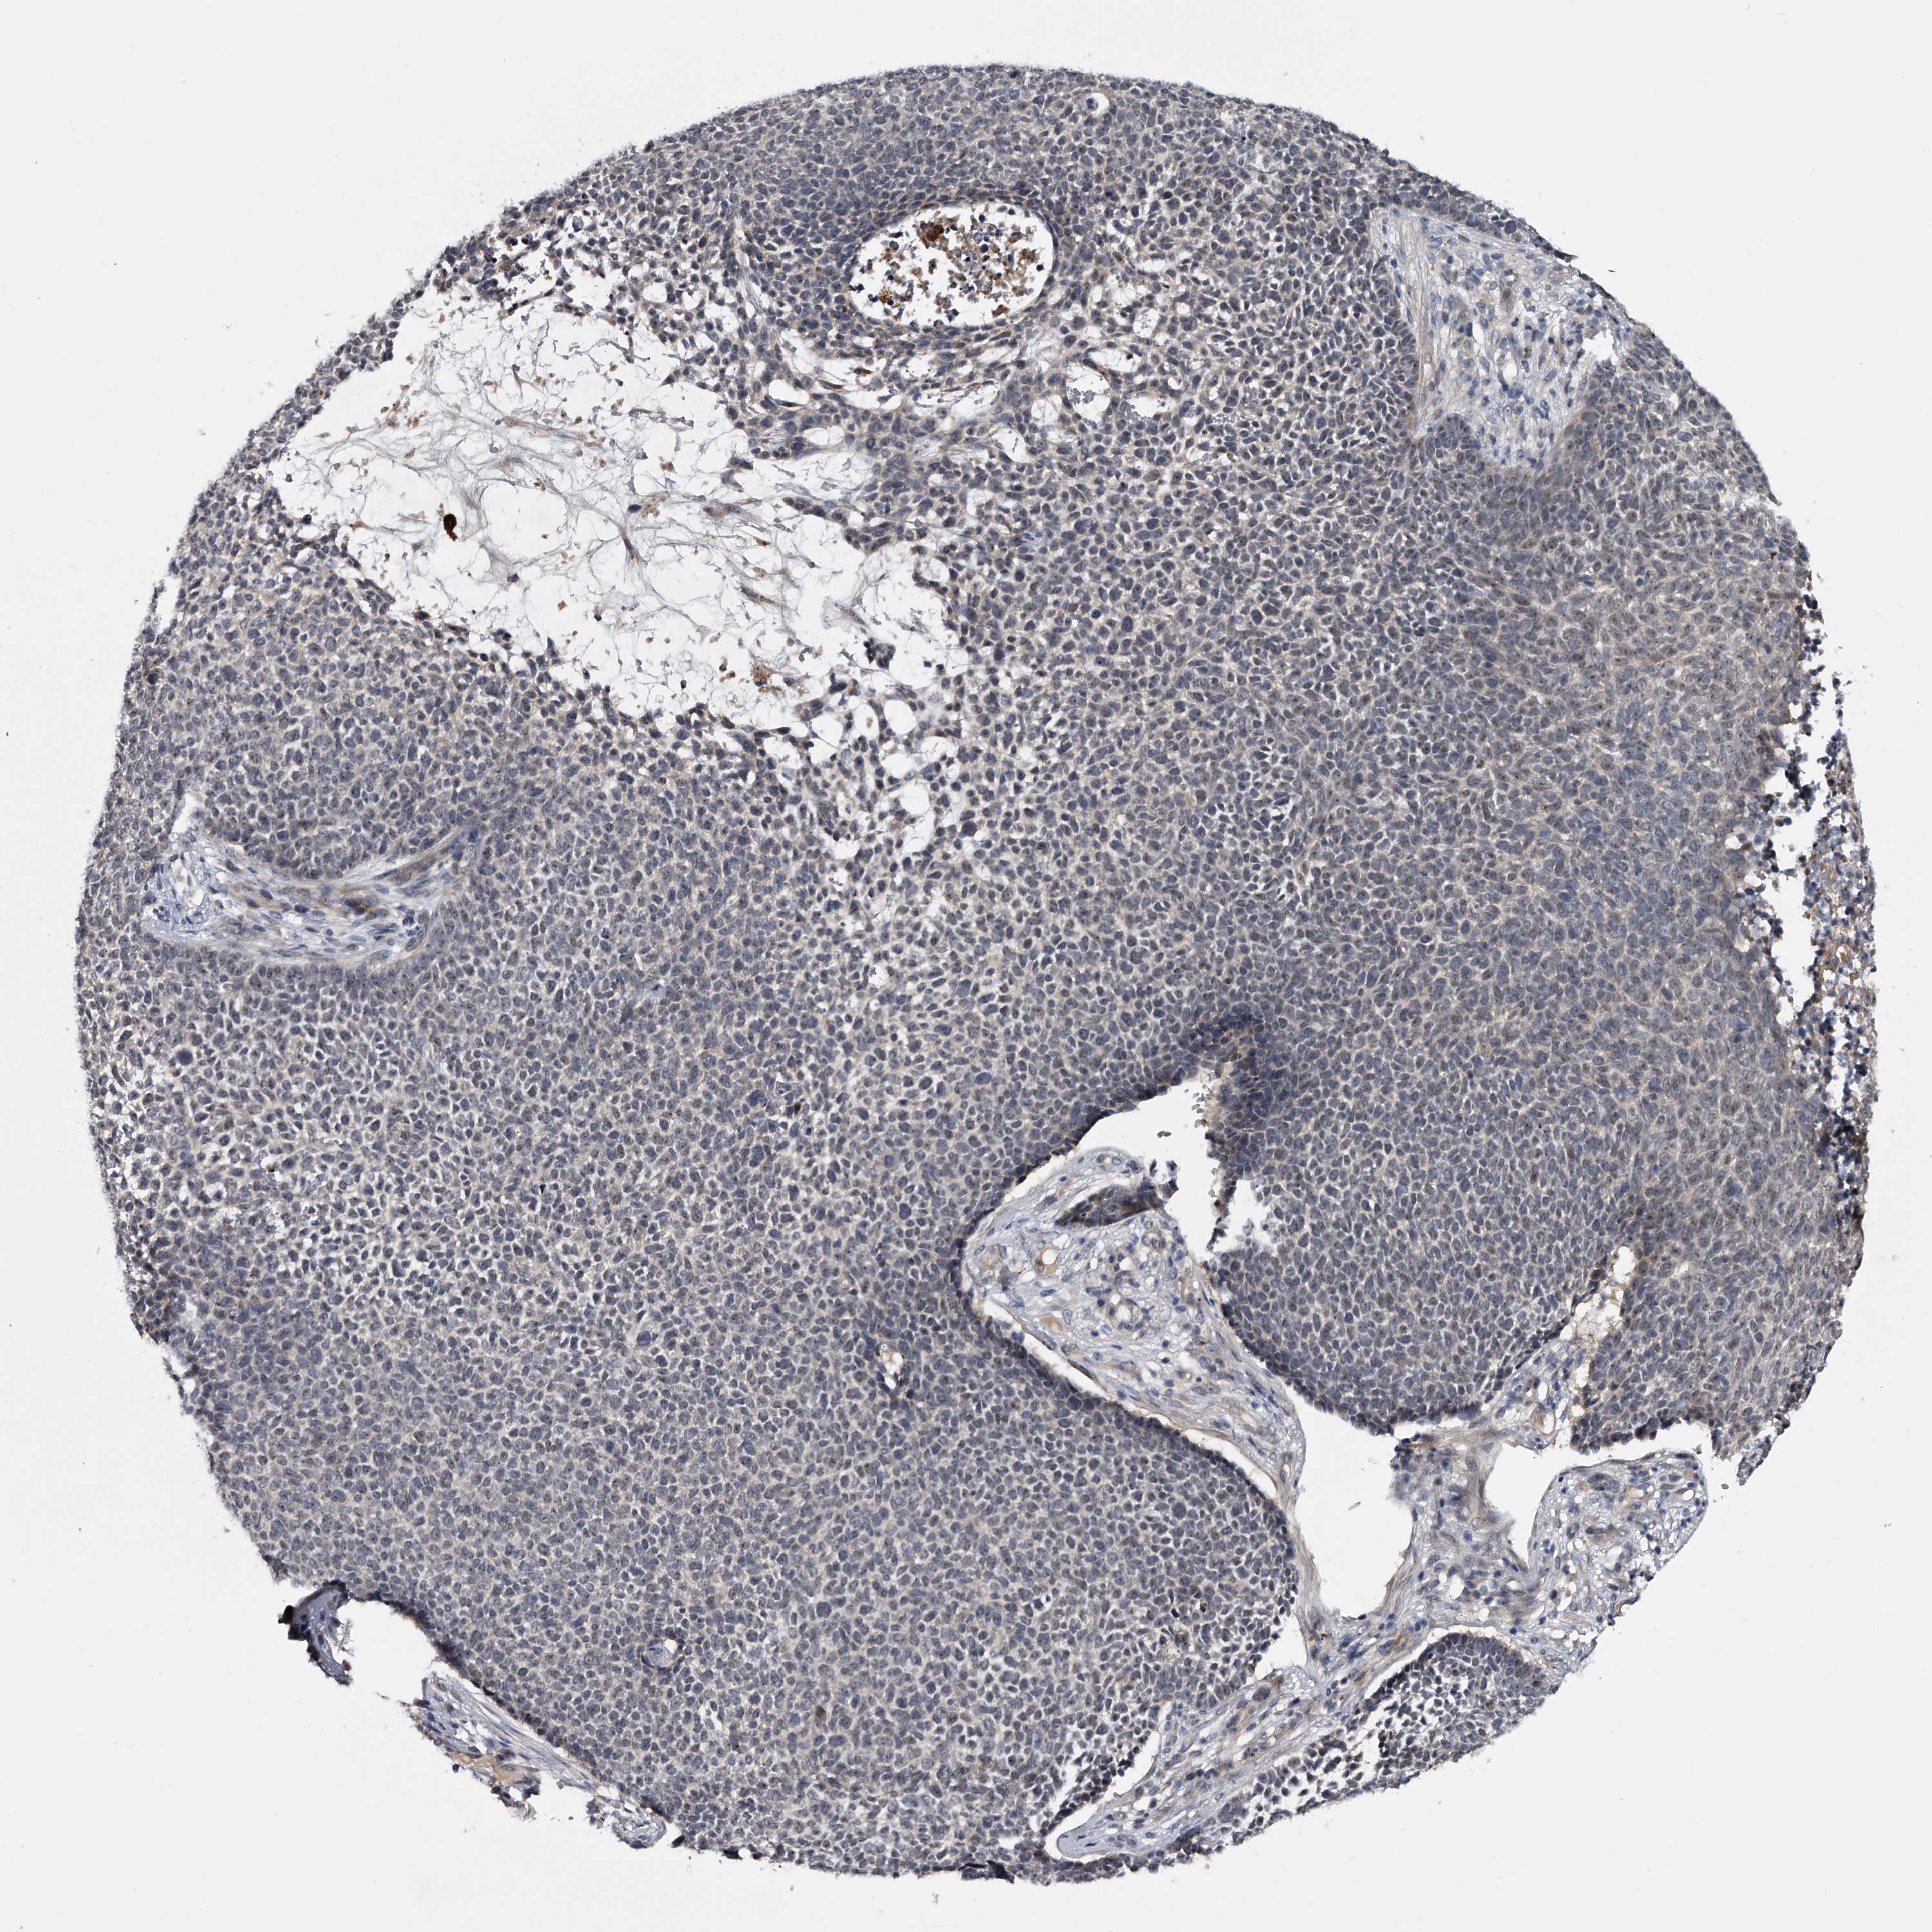

SKIN CANCER - Protein expressioni

A mouse-over function shows sample information and annotation data. Click on an image to view it in a full screen mode. Samples can be filtered based on level of antibody staining by selecting one or several of the following categories: high, medium, low and not detected. The assay and annotation is described here.

Each image is clickable and will lead to virtual microscopy that enables deeper exploration of all samples and also displays staining intensity scores, fraction scores and subcellular localization as well as patient and tissue information for each sample.

Antibody HPA029666

Antibody HPA029667

Antibody HPA029668

Antibody HPA029669

Basal cell carcinoma

Squamous cell carcinoma, NOS

Squamous cell carcinoma, metastatic, NOS